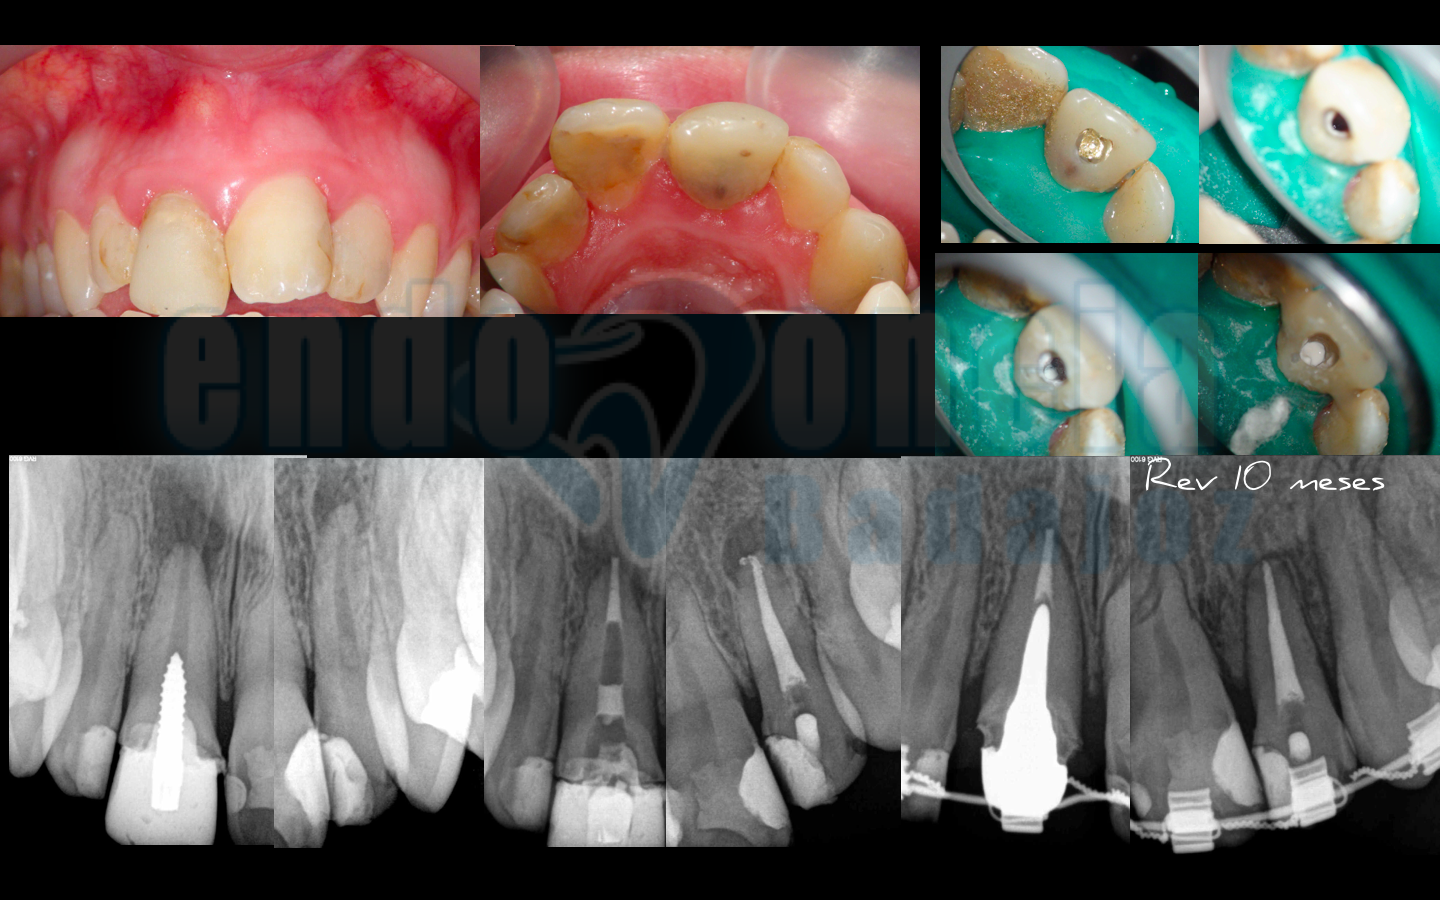

Caso 5:

Sector anterosuperior, tratamiento de un incisivo central con perno de aleación de oro, que decidimos eliminar para tratar el conducto y sellarlo con MTA y un I. lateral , ambos con lesiones apical que a los 10 meses vemos con perfecto estado de salud apical.